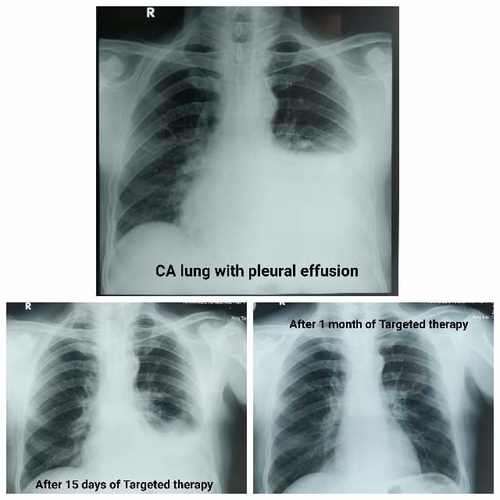

Targeted Therapy in Lung Cancer

With the advent of precision medicine, the treatment of lung cancer has undergone revolutionary discoveries providing simple, oral, and selective and most effective treatment for patients with stage 4 lung cancer.Targeted therapy is:1) Selective on cancer cells2) more effective than conventional treatment on selected patients3) least side effects #stage4LungCancer#TargetedtherapyinLungCancer#OncologistinPune#DrRahulKulkarni.